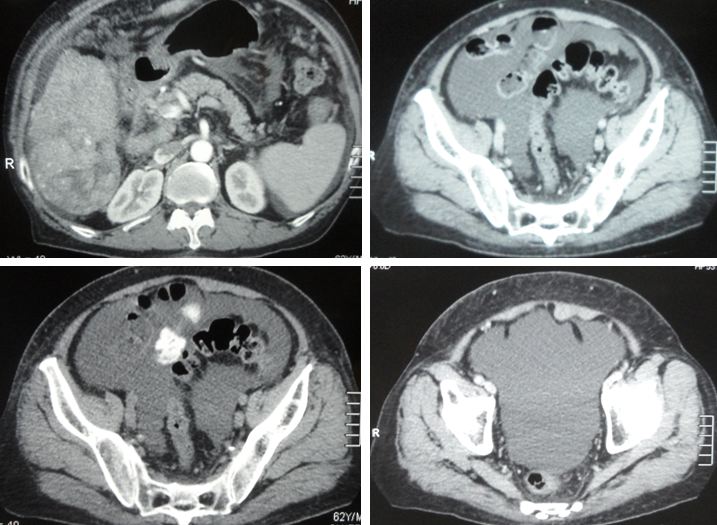

Fast forward to April 2018 – a repeat Triphasic CT scan showed:

- A solitary non-enchancing homogenous isodense liver nodule 3.3 x 3.6 cm. In view of underlying chronic hepatitis carrier, need to exclude atypical hepatocellular carcinoma.

A follow up CT in July 2020 showed:

- Increasing size and number of liver lesions in segment 2 and 3.

- Lung nodules with pleural-based lesions suggestive of lung and pleural metastases.

- Prostatomegaly with chronic bladder obstruction.